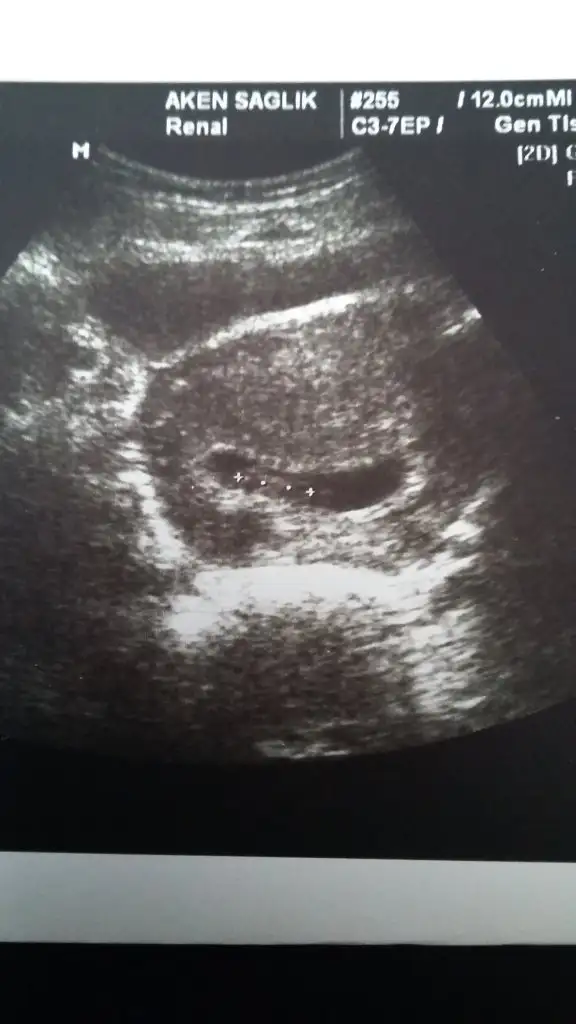

Kızlar ramziye göre plasentanın konumu önemli diye biliyorum.cinsiyeti netleşen arkadaşlar bir bakabilir misiniz?

Plasenta sağ üst veya sağ altta ise erkek

Plasenta sol üst veya sol altta ise kız diye biliyorum.tabi bu karından bakıldığında ters görünüyor ultrasonda,yani ultrasonda karından bakınca sağ sol gibi sol sağ gibi çıkıyor kağıda

Bakalım tutacak mı?

Plasenta nasıl anlaşılıyor ultrasonda. Bunu bi çözsem kavrıycam işi kimi et parçası gibi diyor kimi yay gibi diyor kimi parlaklık diyor